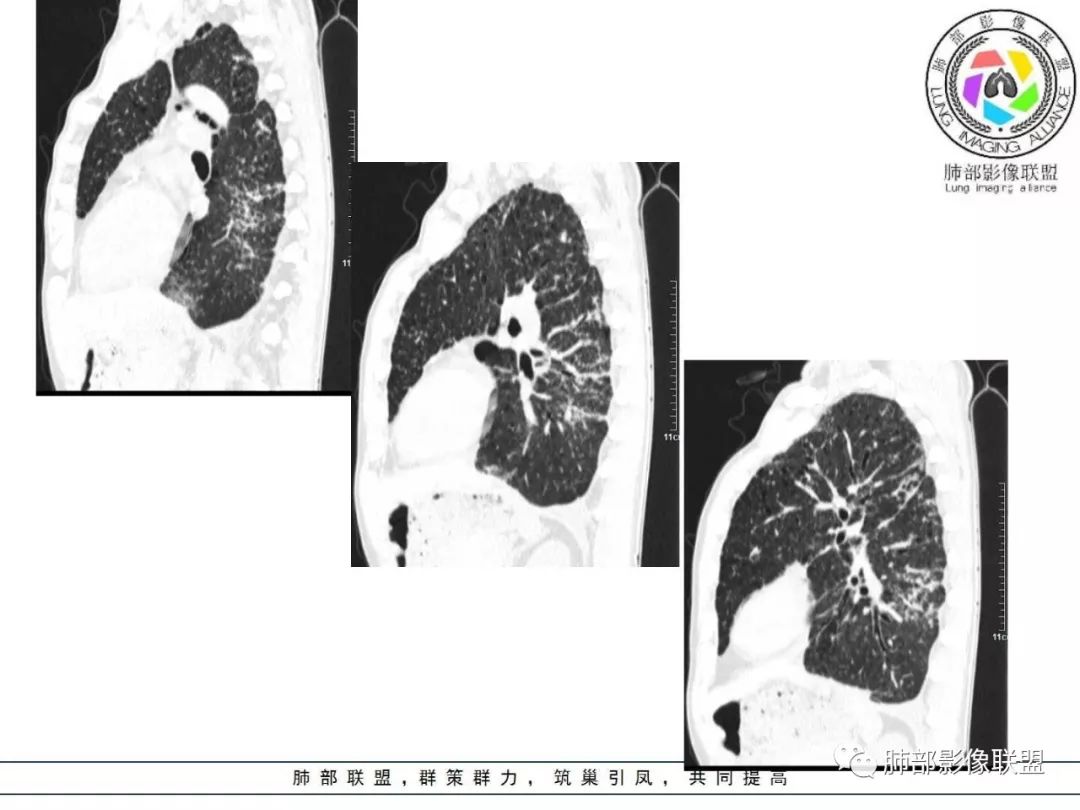

双肺间质性病变,中央间质增厚,胸膜下间质增厚,左侧胸膜肥厚,胸廓变小,肋间隙变窄。

对,大的支气管血管周围

胸部CT:两肺弥漫病灶,磨玻璃影,少许实变,部分累及胸膜,磨玻璃区可见囊?少许胸腔积液,两肺可见结节,支气管血管束增粗,小叶间隔增厚,支气管走形有扭曲扩张,可见纤维化。气肿、大泡。考虑:感染性病变,PCP?查下HIV,CD4,G等。鉴别结核、结缔组织病肺浸润。

胸部CT:两肺弥漫病灶,中央间质分布为主,部分位于胸膜及叶间裂旁,磨玻璃影,斑片影,部分实性结节,肺气囊,支气管血管束增粗,小叶间隔增厚,叶间裂不均匀增厚,支气管走形有扭曲扩张,可见纤维化、气肿、大泡。考虑:LIP加MALT。鉴别PLCH、PCP、结核、结缔组织病肺浸润。

病灶呈片状磨玻璃密度影,呈典型的烟花征。磨玻璃影密度偏高,有网结节样改变,与正常肺实质分界清楚,且常见相对高密度的勾画。

烟花征分为3肿类型:晕征、反晕征及均匀分布。

病变一般沿血管支气管束分布或小叶分布,一般上肺多于下肺(这与常见继发性肺结核分布相若)。

2. 肺气肿背景(小叶中心性肺气肿);双肺多发病灶整体沿血管支气管束及胸膜下分布,以上叶及下叶背段分布为主,有实变及GGO,边界清楚,有树芽,小叶间隔及中央间质增厚,叶间裂见到多发结节,部分支气管不规则牵拉扩张,提示病灶纤维化明显,结合临床病史,考虑病灶为间质性感染,肺门及纵隔内有钙化淋巴结,小叶间隔结节,考虑淋巴道增值性疾病可能,综合常规要怀疑间质性肺结核。